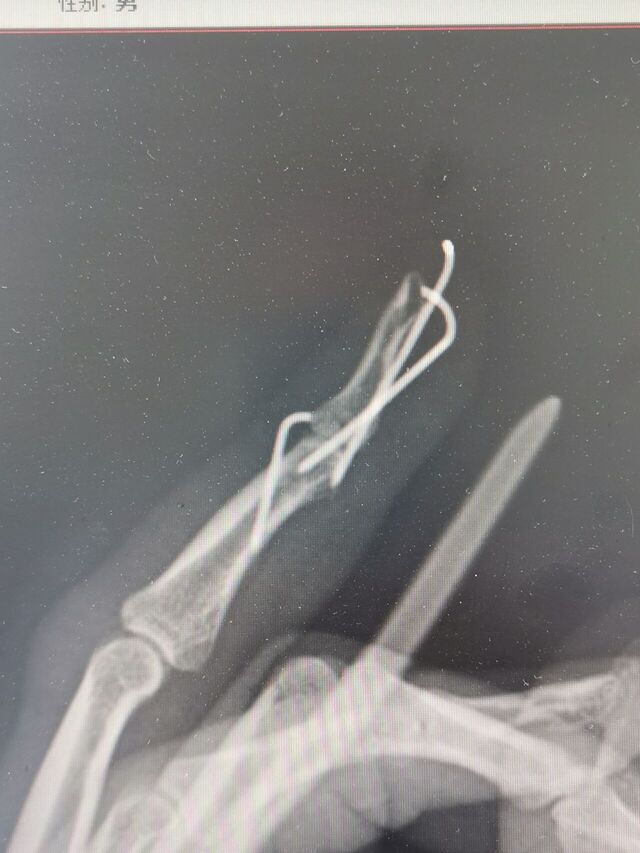

克氏针压扣法治疗骨性锤状指

昨天做了两例

效果都很好